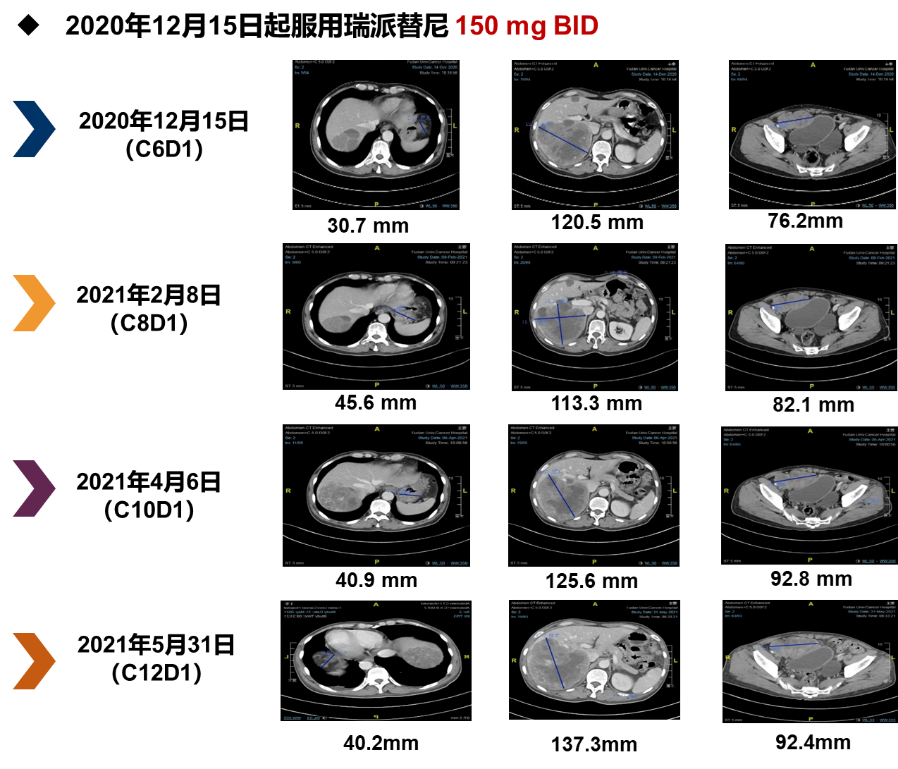

后续治疗(瑞派替尼150 mg BID,2020年12月至2021年6月)93a帝国网站管理系统

2020年12月15日起改为服用瑞派替尼150 mg BID。至2021年5月31日肿瘤病灶仍处于SD状态。期间患者的不良反应主要为1级低钙血症、2级低磷血症和2级贫血。患者继续服药至2021年6月28日因出现3级贫血,按照研究方案剂量调整原则,停用瑞派替尼。至2021年8月17日CT提示肿瘤进展,PFS为8个月。93a帝国网站管理系统

图片